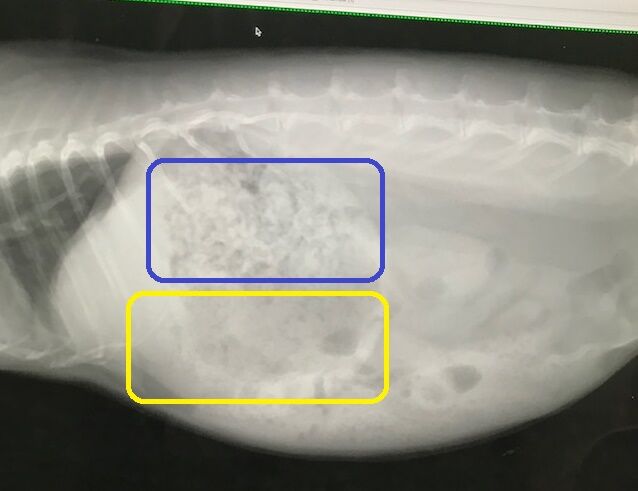

その後も糞はいくつか出てたが食べる方がまったくだったので連行

キャリーがイヤなのか、もしくは相当弱ってるのか、や、痛みに俄然弱いタイプかも?

ので、さすがに胃の張りとかはない

体重は1.96kgで甘えたさんは全開

異変から改善なく通院コースになるのも珍しく、

まあせっかく来たし?点滴もしてもらいました。

ステロイドも少しだけ。